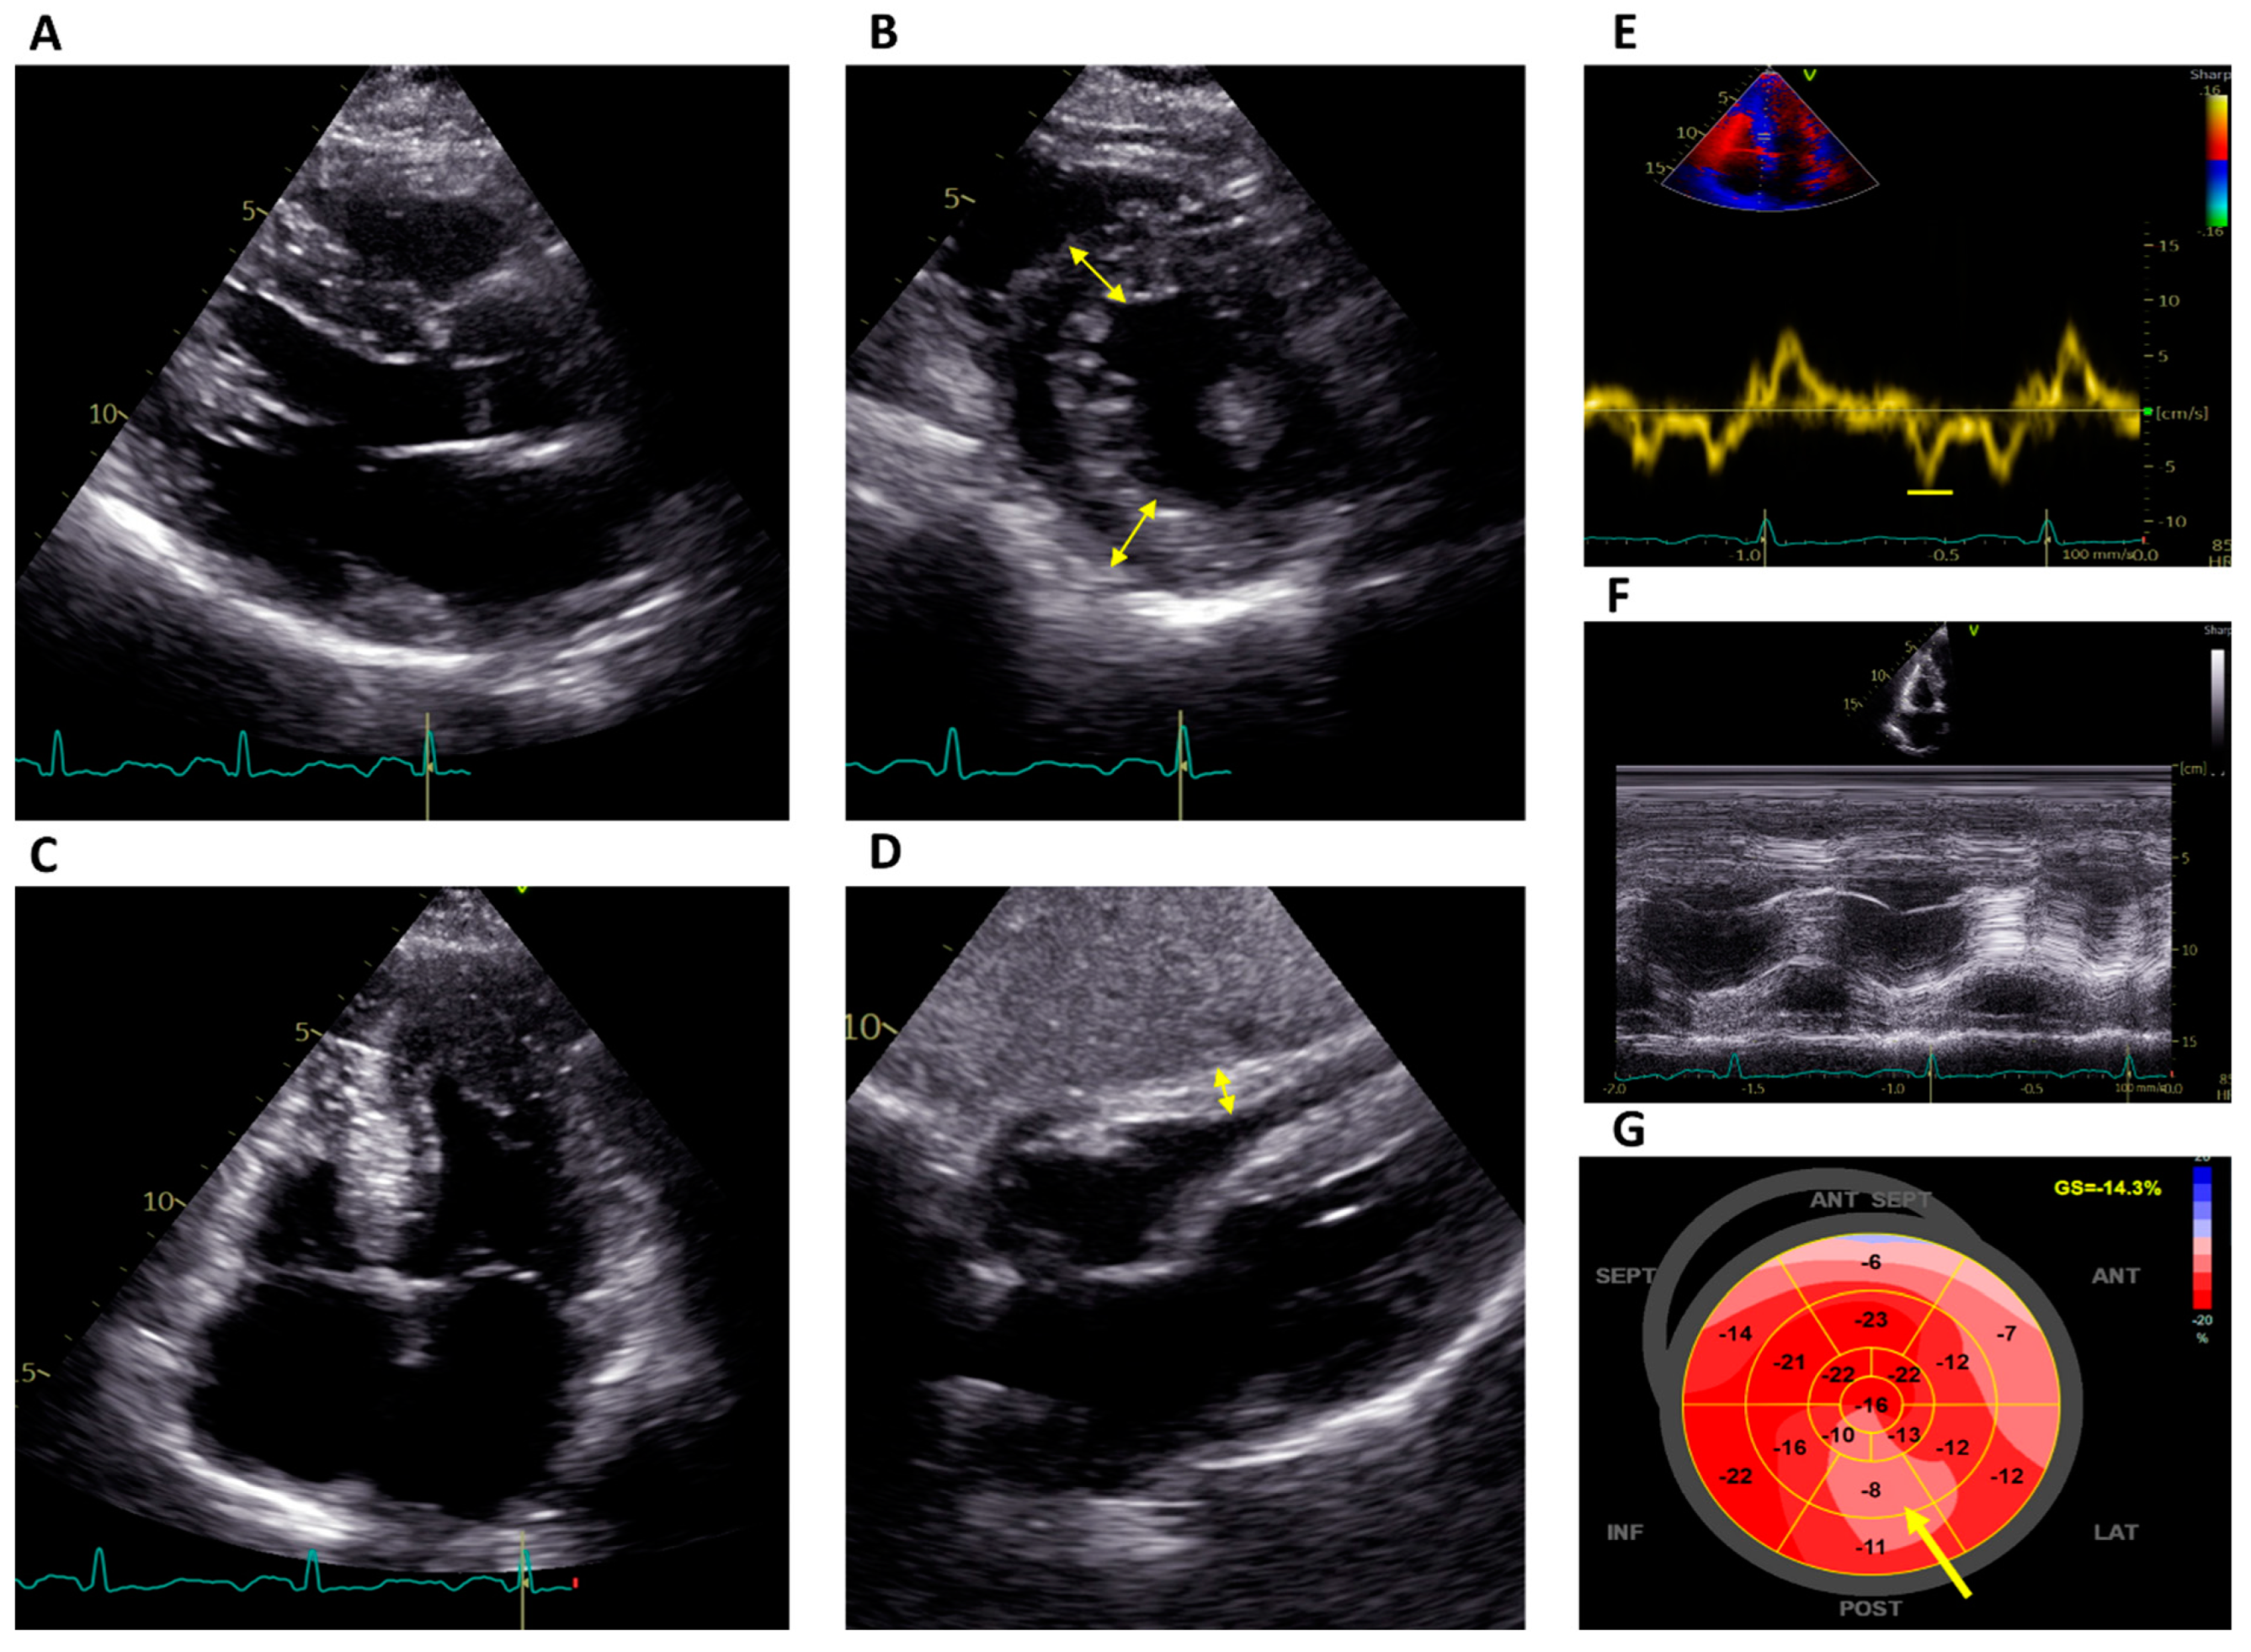

2.1. Echocardiography

3.1.1. Echocardiography

3.2.1. Echocardiography

| Echocardiography | CMR |

| Concentric LV hypertrophy with disproportionate hypertrophy of the papillary muscles [33] | |

| Elevated LV mass [14] | |

| Right ventricular hypertrophy with normal systolic function [15,16] | |

| Reduced tissue Doppler strain [23] | Basal inferolateral LGE [35] |

| Reduced GLS [17,18] | Reduced global native T1 (may be normal or increased in advanced stages) [38,39] |

| Abnormal basal inferolateral regional strain [19] | Normal ECV (may be increased in advanced stages) [43] |

| Loss of basal-to-apex circumferential strain gradient [22] | Elevated T2 in the basal inferolateral wall [44] |

| LA dilation (not specific to FD) [26] | |